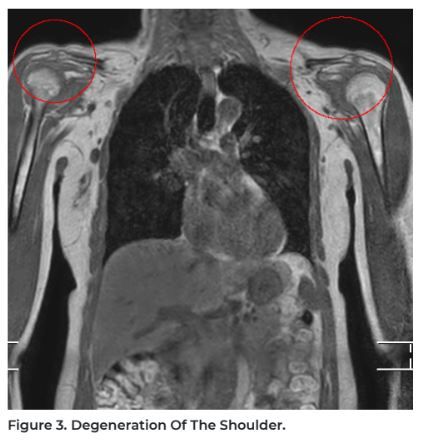

4. Musculoskeletal Problems: Joint and muscle conditions, including tears, degeneration, and inflammation.